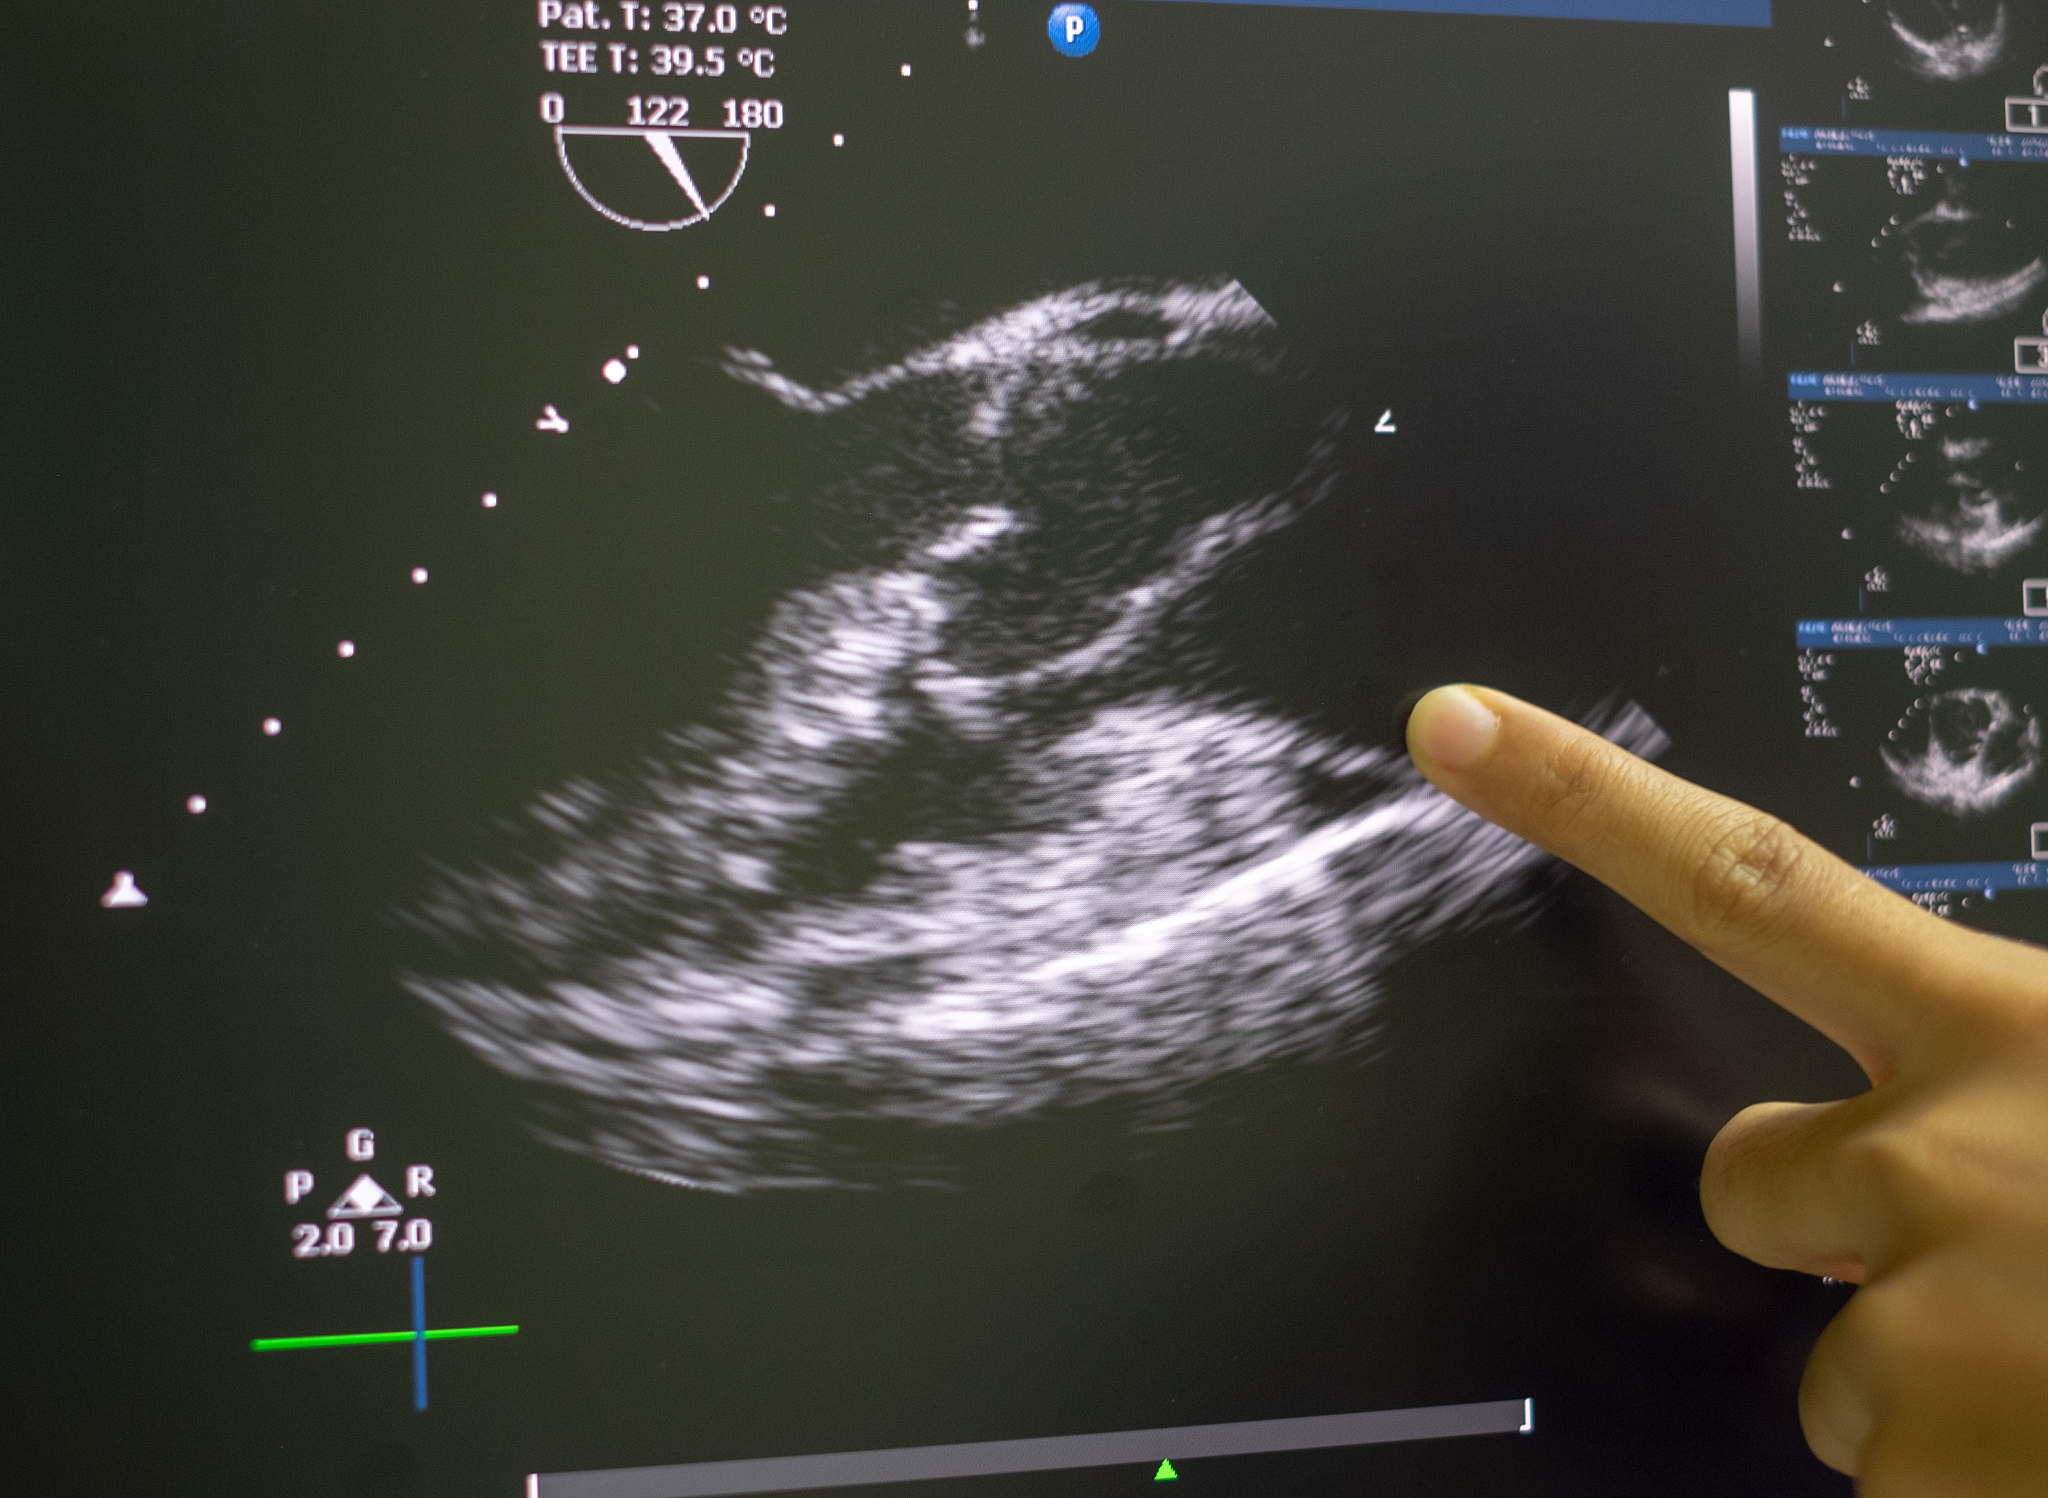

血管内超声诊断导管是一种用于血管内超声诊断的医疗器械,市场需求主要来自心血管疾病、神经血管疾病等方面。目前,国外市场占据了血管内超声诊断导管市场的主导地位,但是随着中国医疗行业的不断发展和改革,国内市场也在逐渐增长。

血管内超声诊断导管的市场现状国外和国内的市场占比等信息